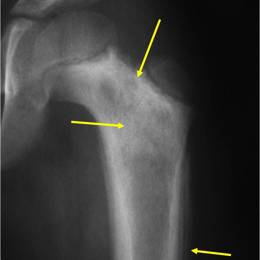

• • The work-up for Ewing's Sarcoma often consists of a physical examination, X-rays, CT scans, or MRI of the effected bone. A Whole Body Bone Scan may be ordered to determine if the tumor metastasized, or spread.

Ewing's Sarcoma is an aggressive, cancerous (malignant) tumor that, if left unchecked, will grow and destroy the normal bone. Clinically, they manifest as localized pain (usually worse at night), fever, and swelling. The affected area may be tender and warm. Patients may also notice night sweats and weight loss. Early and effective treatment is essential, as Ewing's Sarcoma also has the ability to spread to other parts of the body, known as metastasis. Advanced imaging, such as whole body bone scans and CT of the chest/abdomen/pelvis, are used to check if the cancer has spread, or metastasized, throughout the body.

An example of an MRI depicting Ewing's sarcoma in the lower extremity is shown.